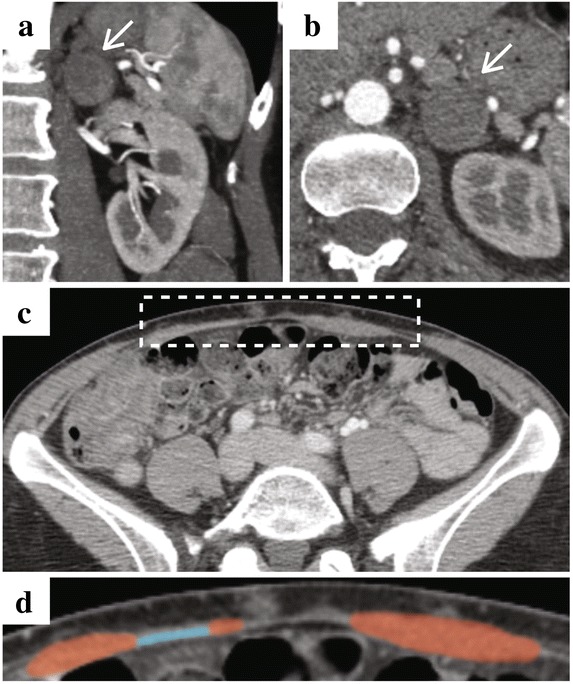

Fig. 3.

Computed Tomographic Imaging Prior to Laparoscopy Following Breast Surgery. a Coronal and b axial images demonstration left-sided pheochromocytoma. c Low-magnification axial image of the abdomen (white box highlights anterior abdominal wall). d High-magnification axial image of the anterior abdominal wall (red and blue indicate rectus abdominis muscle and mesh, respectively)

Figure 3. Computed Tomographic Imaging Prior to Laparoscopy Following Breast Surgery.